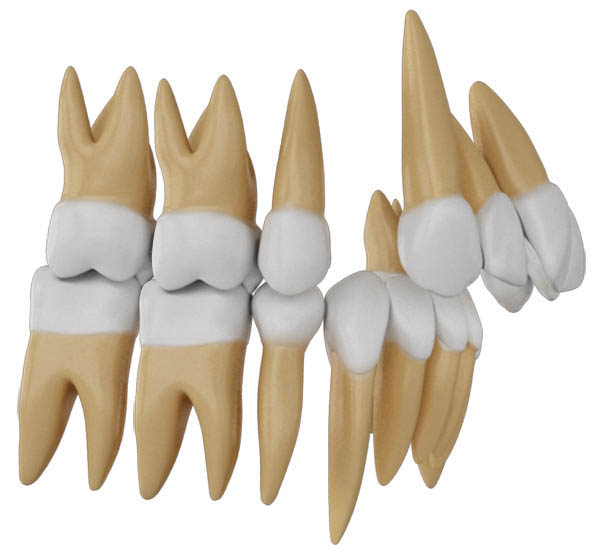

شکل 124-2: پرمولر پایین کشیده شده و فضا بسته شده است و خلف پایین نیم کاسپ حرکت مزیالی نموده و اکلوژن را کلاسI نمود.

شکل 125-2: پرمولر بالا کشیده شد و چون باید اکلوژن کلاسI تمام بشود، لذا خلف بالا اصلاً نباید حرکت مزیالی نماید پس نیاز به مینی اسکرو دارد.